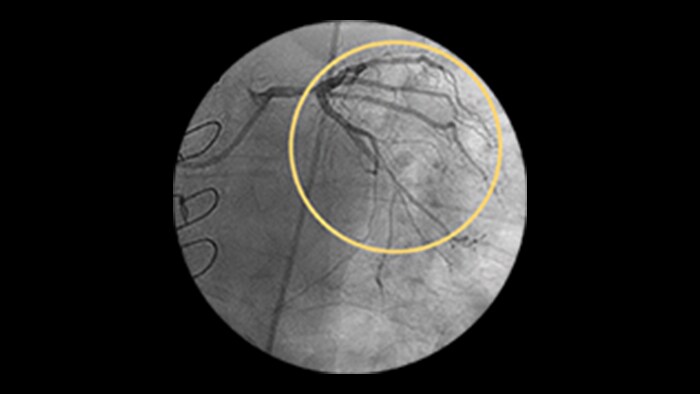

Diffuse Disease

Approximately 20% of the coronary lesions treated today are long and diffuse.1,2

Clinical challenges

– Stent length is an independent predictor of in-stent restenosis and thrombosis.

– Stenting long segments with multiple and or overlapping stents may lead to injury to the vessel wall integrity.

– Diffuse CAD may be underestimated by evaluation with coronary angiography.

– Determining reference vessel sizing can be challenging when the vessel is diffusely diseased.

IVUS-guided vs. angiography-guided outcomes3